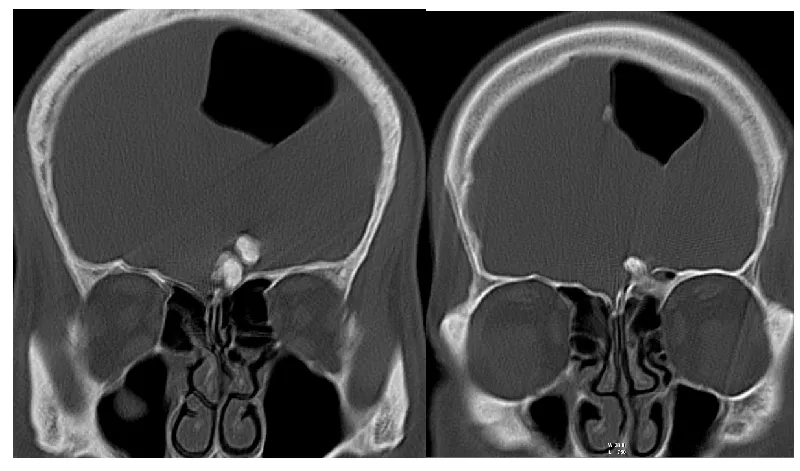

A 46-year-old man was admitted to the hospital with a persistent headache in the frontal area lasting approximately one year which was resistant to analgesics. His physical and neurological examination was normal. After written consent, Cranial Computed Tomography (CT) was performed to exclude the intracranial pathology and revealed large intracranial extra-axial air collection extending to the vertex with no evidence of other intra-axial pathology. Abnormal lobulated calcification is seen in the vicinity of the frontoethmiod region (Figure 1).

The subsequent true cranial view is obtained and revealed the aforementioned air collection is transported to the parietal region (Figure 2), and bone window reformatting shows a well-defined macro-lobulated bony projection is seen extending from the anterior ethmoidal sinus projecting intracranially (Figure 3).

A crack in the superior wall of the ethmoidal sinus is noted arrow in Figure 2 and explains the formation of the intracranial air collection.